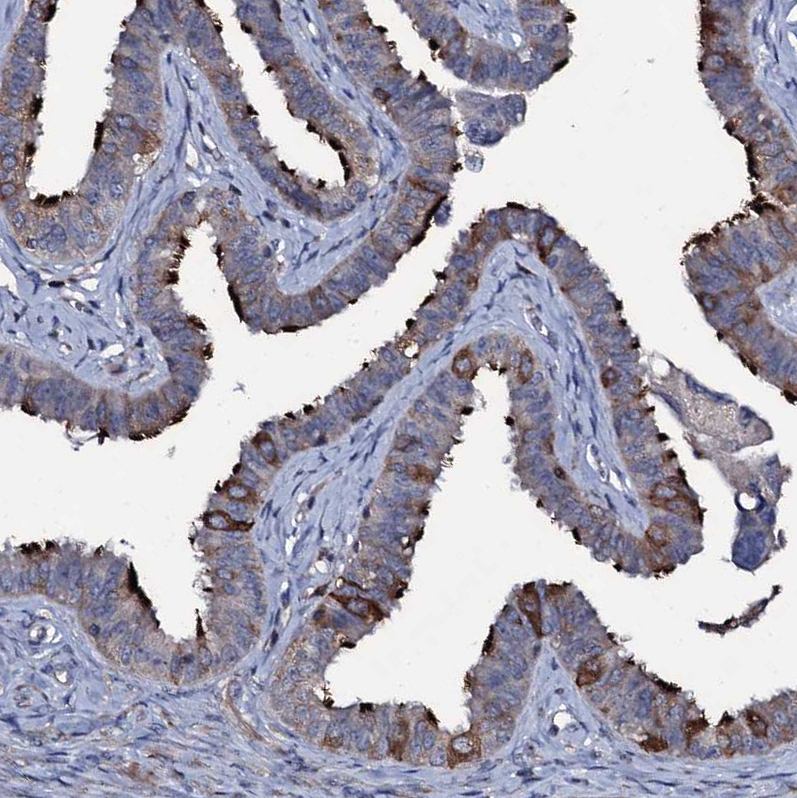

Immunohistochemical staining of human fallopian tube shows strong positivity in cilia in glandular cells.